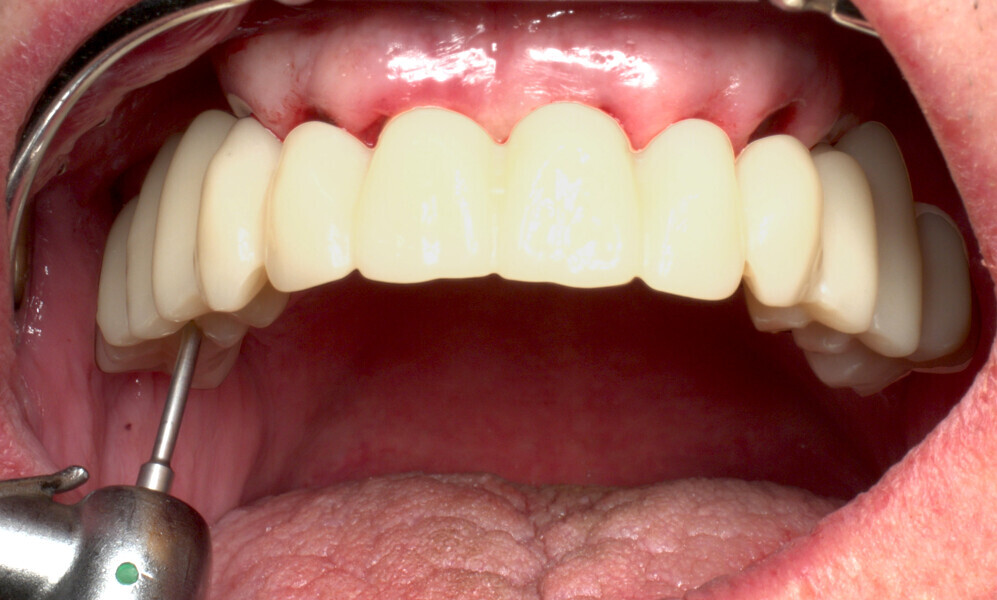

The fully digital Pro Arch protocol